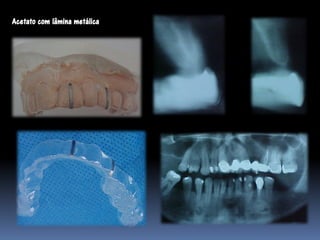

Guia radiográfico

-posição ótima do implante com marcadores

radiopacos

•Guta percha

•Esferas e tubos metálicos

•Fios e lâminas metálicas

•Lâmina chumbo do RX

•Dentes de sulfato de bário

•Facilita perfuração, paralelismo e distribuição dos

implantes

•Elimina a medição entre implantes

•Permite alternar as possibilidades de instalação

•Vácuo- press ou própria prótese do paciente

duplicada com acrílico transparente

Marcadores radiopacos

Esferas

Tubos

Guia radiológico

Dentes de sulfato de bário

Acetato em vácuo-press

Acrílico com tubos

Acetato com lâmina metálica